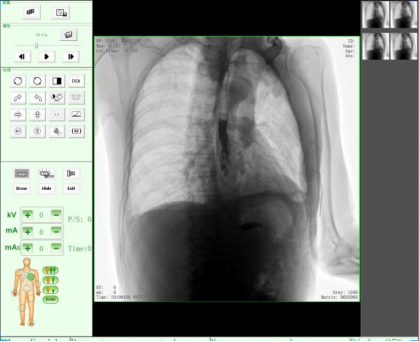

三、醫學用途,醫用X射線機作為醫學診斷重要的設備之一,目前市面上醫用X射線機種類主要有DR、CR、C形臂、乳腺機、胃腸機、口腔CBCT等醫療器械。設備依據X射線的穿透作用、差別吸收、感光作用和熒光作用,利用人體各組織的密度和厚度不同,通過檢測圖像陰影濃淡的對比,結合臨床表現、化驗結果和病理診斷,即可判斷人體某一部位/內部器官是否正常。此類X光機廣泛應用于醫療機構與場所,為相關單位提供了快速的醫療診斷。

DR